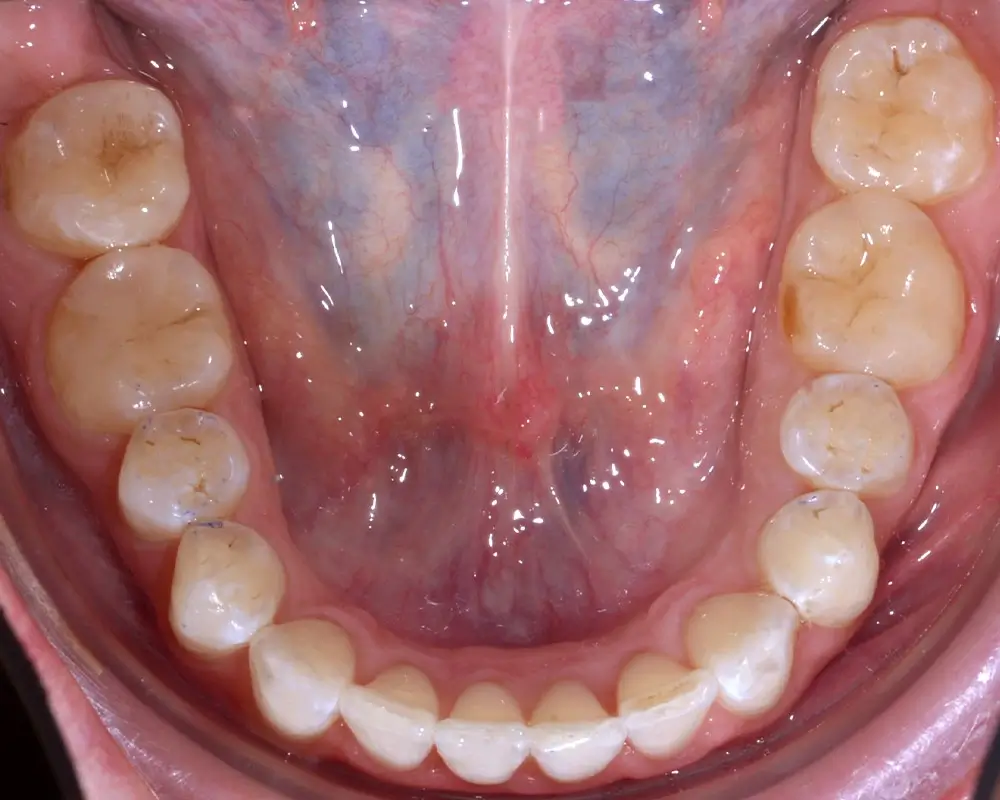

Кейс 1

Количество кап ВЧ 25

Количество кап НЧ 25

ДО

ПОСЛЕ